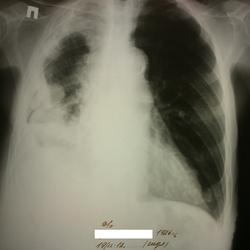

На рентгенограмме признаки гидроторакса справа, проведена плевральная пункция, установлен дренаж. Получено 2000 мл серозно-геморрагической жидкости.

После плевральной пункции проведено контрольное рентгенологическое обследование.

1. при поступлении

2. после пункции